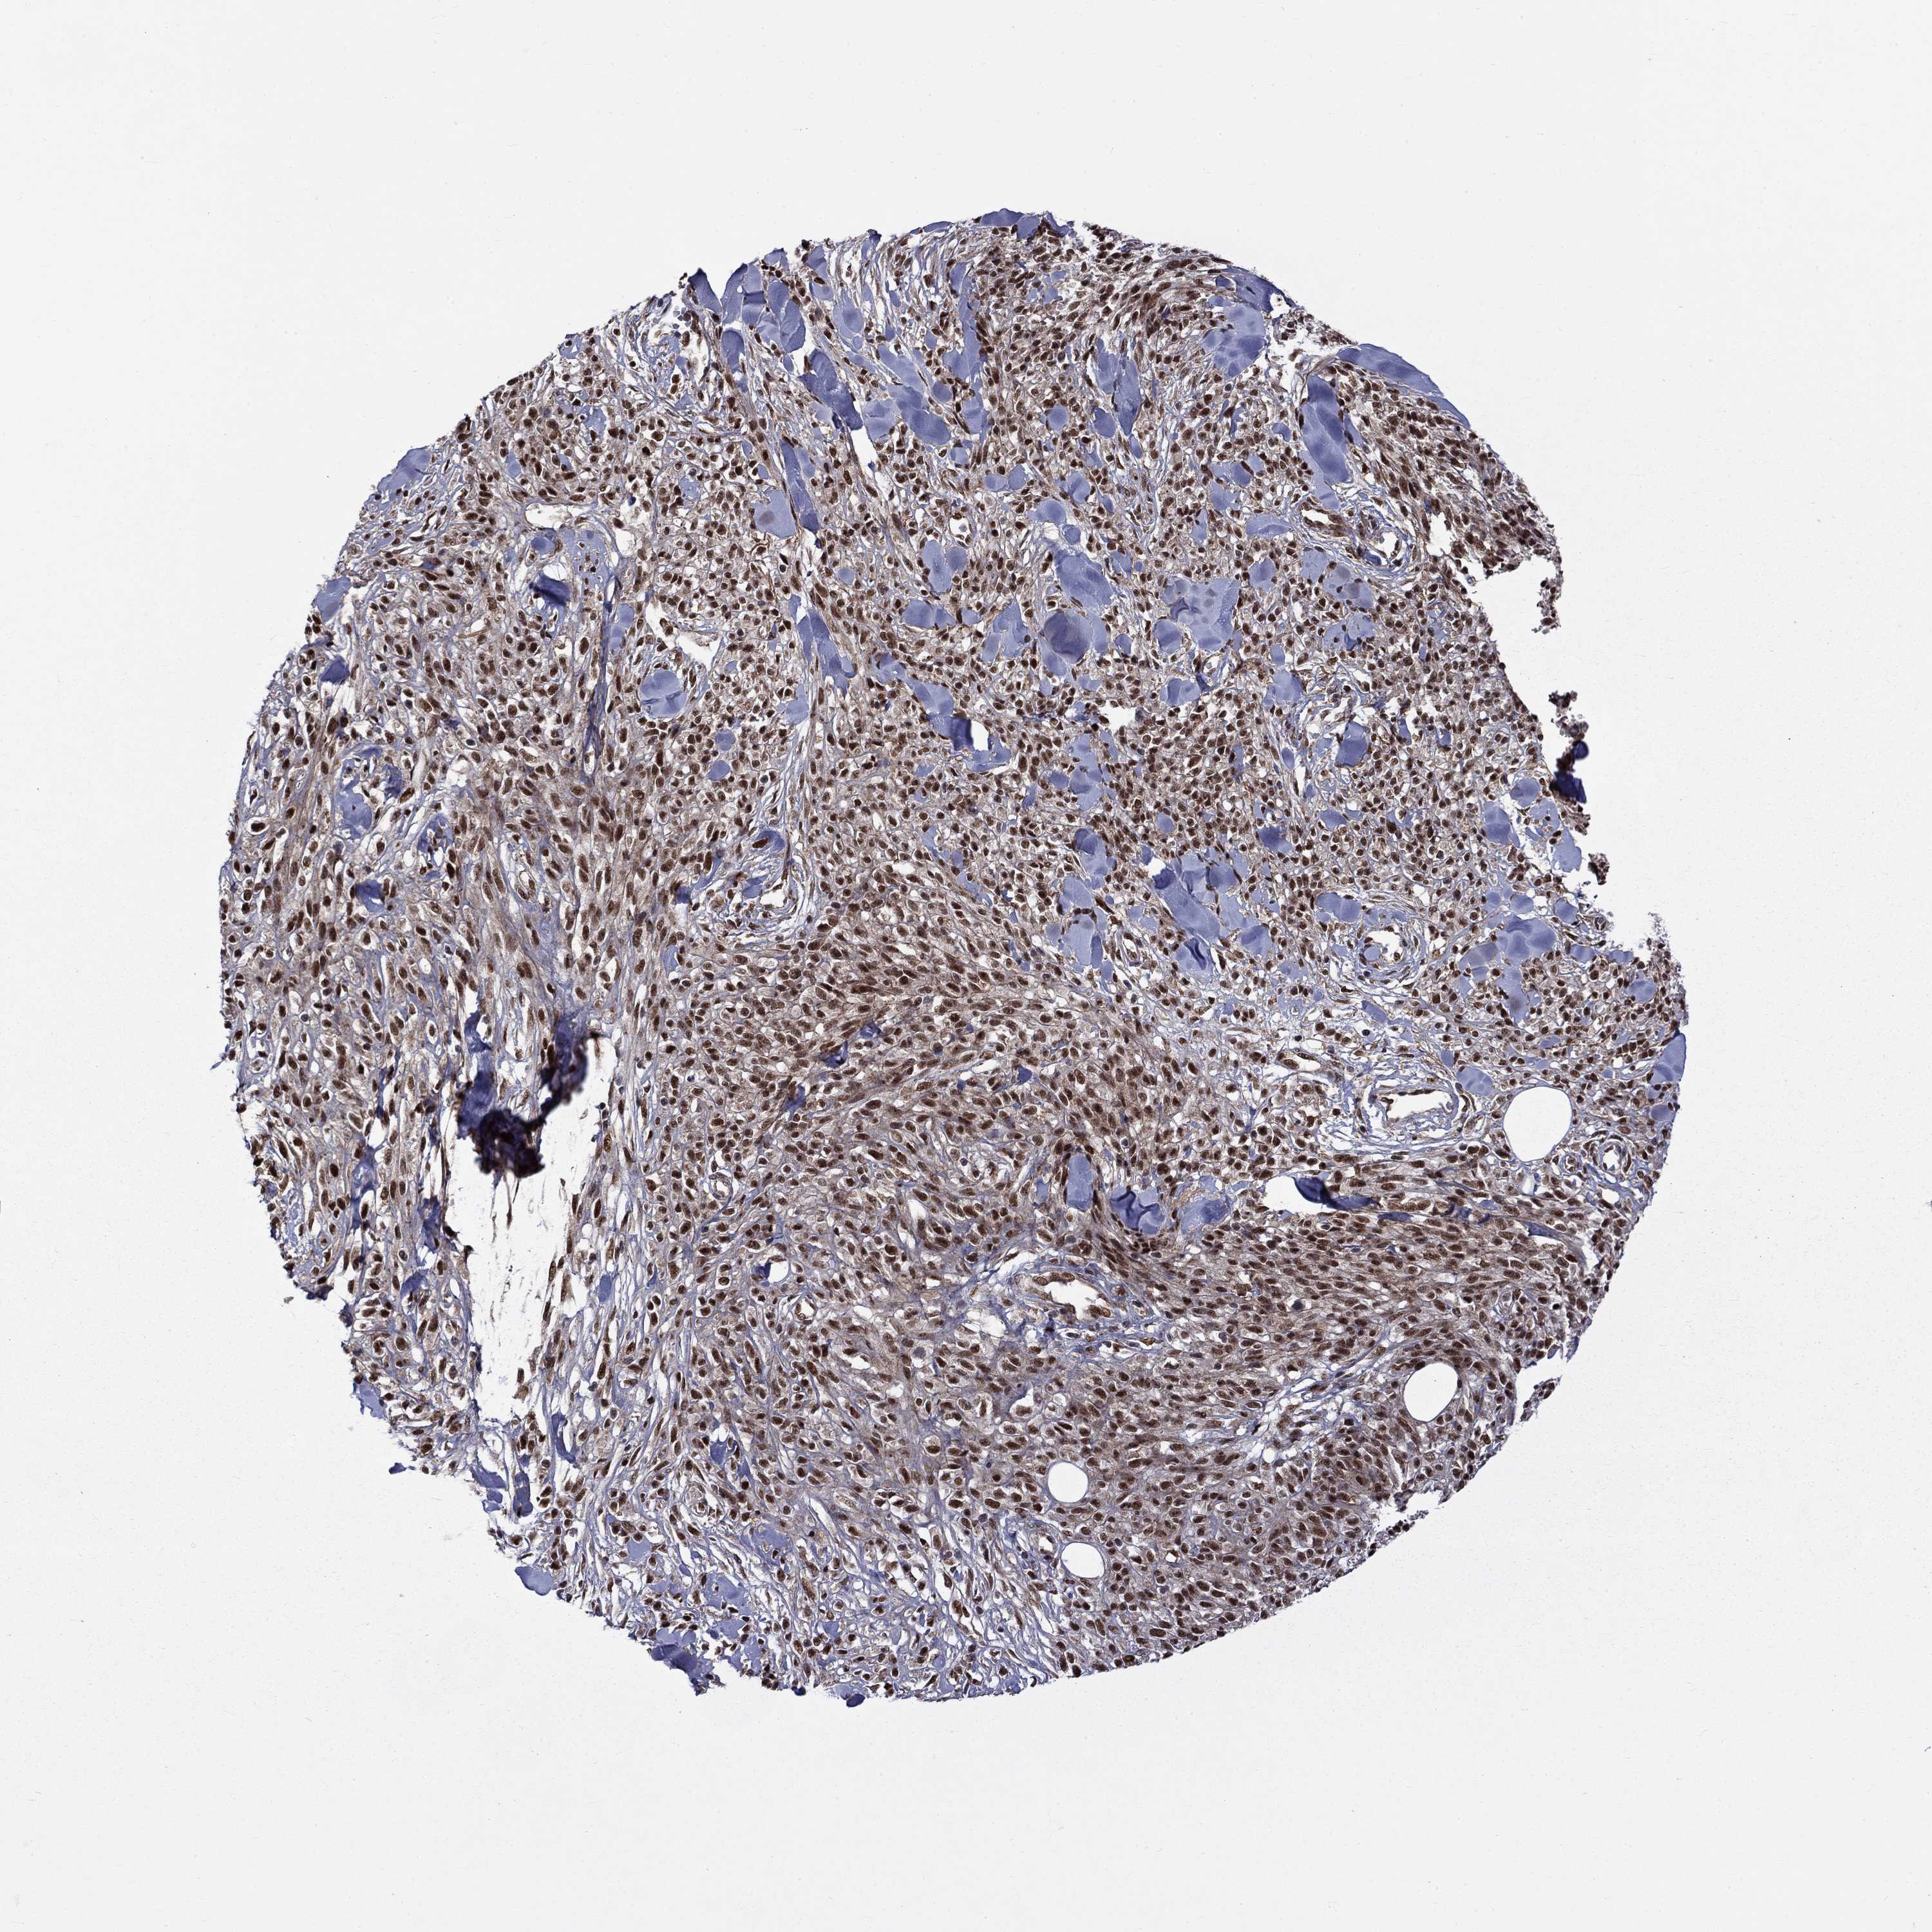

MELANOMA - Protein expressioni

A mouse-over function shows sample information and annotation data. Click on an image to view it in a full screen mode. Samples can be filtered based on level of antibody staining by selecting one or several of the following categories: high, medium, low and not detected. The assay and annotation is described here.

Note that samples used for immunohistochemistry by the Human Protein Atlas do not correspond to samples in the TCGA dataset.

Antibody stainingi

Antibody staining in the annotated cell types in the current human tissue is reported as not detected, low, medium, or high, based on conventional immunohistochemistry profiling in selected tissues. This score is based on the combination of the staining intensity and fraction of stained cells.

Each image is clickable and will lead to virtual microscopy that enables deeper exploration of all samples and also displays staining intensity scores, fraction scores and subcellular localization as well as patient and tissue information for each sample.

Antibody HPA046852

Antibody HPA077643

Staining

High

Medium

Low

Not detected

Intensity

Strong

Moderate

Weak

Negative

Quantity

>75%

75%-25%

<25%

None

Location

Nuclear

Cytoplasmic/membranous

Cytoplasmic/membranous,nuclear

Malignant melanoma, NOS

Malignant melanoma, Metastatic site